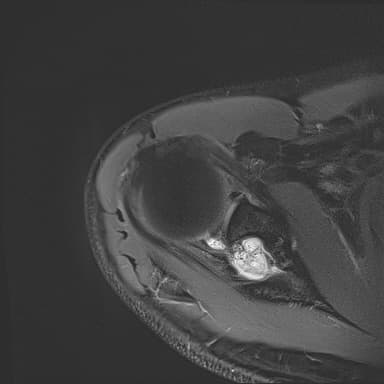

어깨 mri 좀 봐주세요 물혹있다고 하는데 수술해야 하나요?

하도 안 나아서 우측 견관절도 mri 촬영을 했는데 물혹이 있네요

• 2번 째 사진